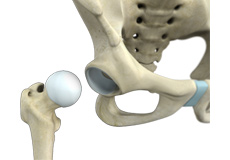

Surgical Hip Dislocation

Surgical hip dislocation is an orthopedic surgical procedure in which the head of the thigh bone is displaced from the hip socket in the pelvic bone. It gives the surgeon a 360-degree view of the hip joint.